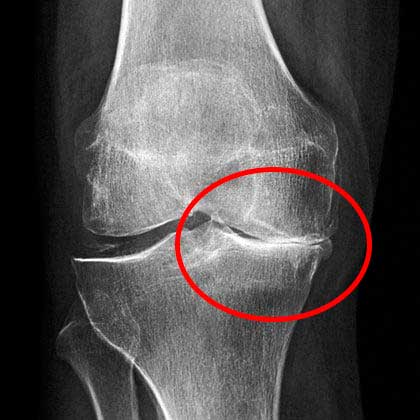

รูปภาพ: ภาพรังสีเอกซ์ของข้อเข่าก่อนและหลังทานแคปซูล Movinix

ผลลัพธ์การรักษาข้อเข่า